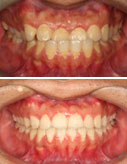

“牙缝大”不开心-瓷贴面7天让你美丽无忧

15岁小帅哥全口虫牙 根管修复露笑颜

不要等牙疼时才想起保护

龋齿不可大意 牙髓炎太可怕

治疗牙周病 还得早着手

只想变美 那就现在

健康爱美的大门前没有“男士止步”

收拾小龅牙 最正确的决定

小小种植牙 托起大梦想

种牙种健康 最美夕阳红